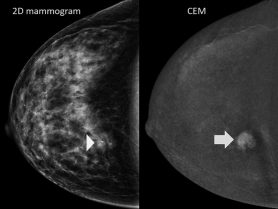

2D digital mammography and 3D digital breast tomosynthesis are the main imaging technologies used for breast cancer diagnosis and screening. However, for some women this may not be enough. If that’s the case for you, your doctor might recommend another kind of mammogram called a contrast-enhanced mammogram.

A contrast-enhanced mammogram (CEM) is just like a regular mammogram, but with an additional step. Before receiving a mammogram, you get an IV injection of iodine-based dye. The dye highlights abnormal blood vessels and hyperactive tissues that can happen when cancers develop. Contrast-enhanced mammograms can evaluate the functional state of breast tissues much like breast MRI can. This enables us to detect breast cancer early.

Dense breast tissue and cancer can be hard to tell apart with traditional mammograms. Dense tissues can hide small masses and make it difficult to detect breast cancers early. Contrast-enhanced mammograms are much less affected by breast density than conventional mammography. This makes them a valuable imaging tool for women with dense breasts.